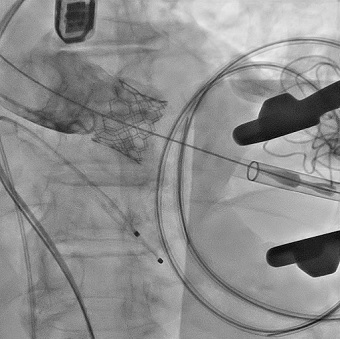

上段:三次元マッピングによる低電位領域の検出。

下段:QRS波より70 ms先行した異常電位を検出。同部位への通電にて心室頻拍は停止した。

図2.アブレーションによる心室頻拍の停止